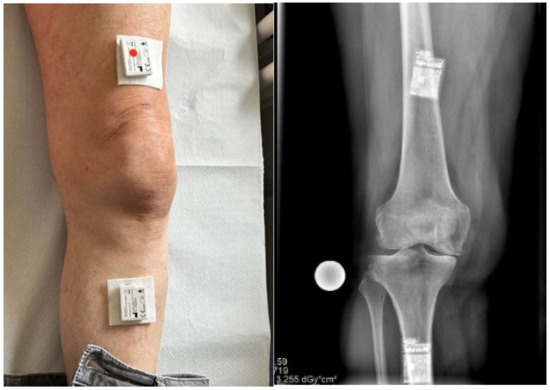

2.2. Inertial Measurement Units

2.3. IMU Application and Measurements